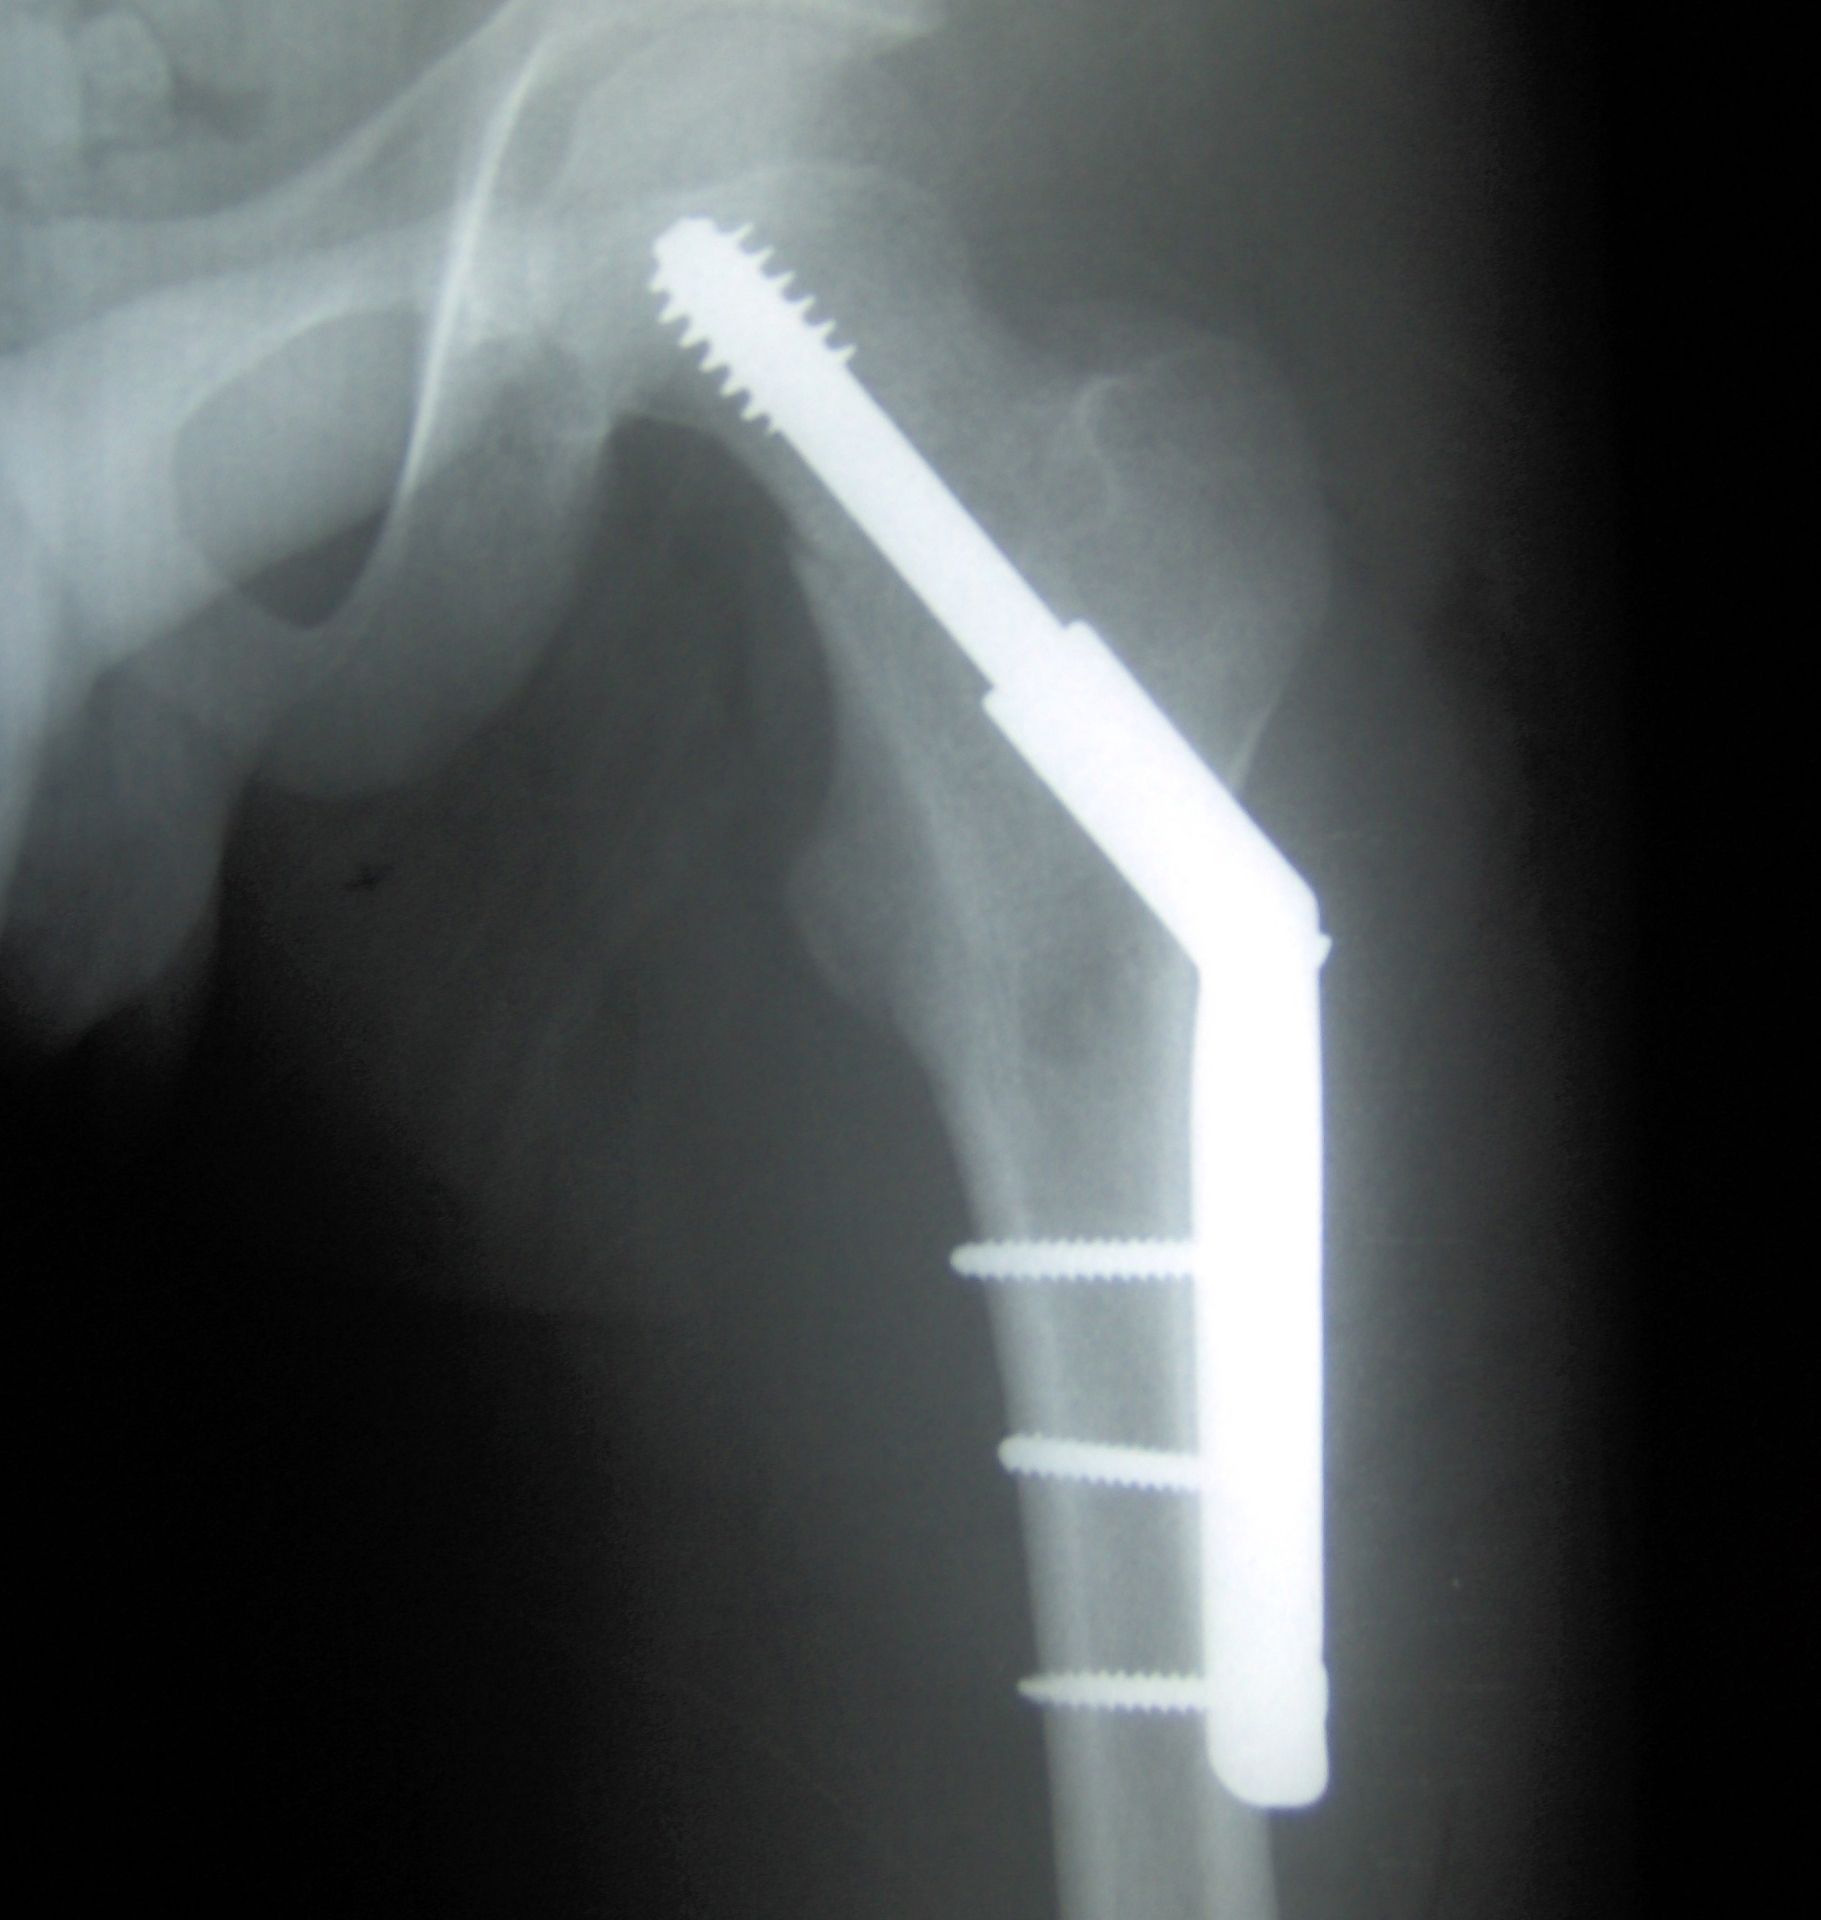

Метод обработки кобальтового сплава, используемого для имплантатов тазобедренных суставов, штифтов, пластин и других биомедицинских изделий, позволяющий улучшить их характеристики, предложили специалисты Национального исследовательского технологического университета «МИСИС» (НИТУ МИСИС), 17 января сообщает пресс-служба вуза.

Сплавы системы кобальт-хром-молибден востребованы при производстве наиболее нагруженных ортопедических имплантатов из-за их высокой прочности, биосовместимости, износо- и коррозионной стойкости.